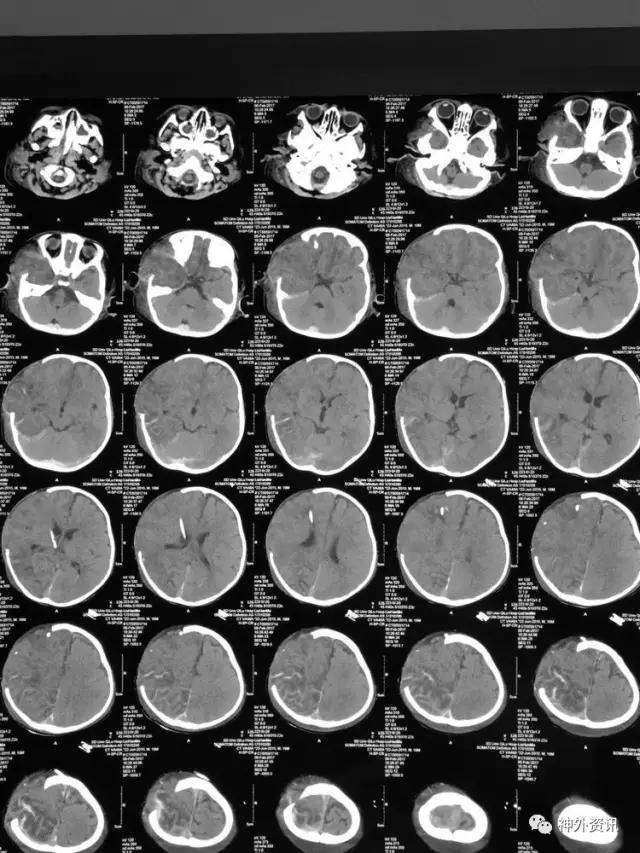

患儿刘**,男,19个月,2017.1.30 2pm不慎摔倒,意识障碍,刺痛不睁眼,不发音,刺痛肢体屈曲,急至当地医院,伤后1小时颅脑CT结果示右额颞顶枕急性硬膜下血肿,中线轻微左移:

3小时后转至我院急诊科,当时查体:刺痛不睁眼,不发音,刺痛右侧肢体屈曲,右侧瞳孔5mm,对光反应消失,左侧瞳孔0.3cm,对光反应迟钝,立即术前准备并复查CT,结果示右额颞顶枕硬膜下血肿,右侧大脑半球及左侧额叶弥漫性低密度,考虑缺血,中线左移明显,脑沟及环池显示不清:

术后移动CT结果示中线移位较术前减轻,顶枕部蛛网膜下腔出血:

2017.2.1:术后2天复查颅脑CT,结果示中线居中,右侧半球低密度并SAH,左侧半球未见明显异常,左侧脑沟可见显示,双肺少量炎症,不能放松警惕,继续同前治疗。

2017.2.4:术后5天复查颅脑CT,结果示中线居中,左侧半球及环池显示清晰,右侧半球脑沟显示欠清晰,脑组织低密度较前有所好转,继续同前治疗。已加用预消化肠内营养液及促进胃肠动力药物。

2017.2.6:术后7天,复查颅脑CT示情况较前进一步好转,逐步撤掉冰毯,缓慢自然复温。

2017.2.8:术后9天,复查颅脑及胸部CT,结果显示双侧脑沟脑回及环池显示清晰。颅压控制,拔除引流管探头,头部敷料稍加压包扎,此时已更替力月西为丙泊酚,停用呼吸机。